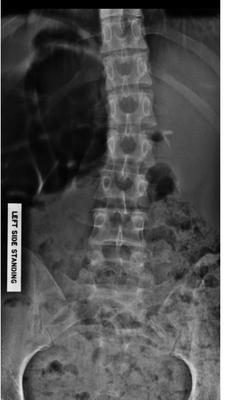

Spine front on 2017

Your lumbar spine has an anomaly called a lumbarisation - six vertebrae instead of five. What is good is that the L6 appears well nested, but there are accessory joints visible, all likely to cause pain periodically.

And thirdly there's a suggestion of a short leg giving you a significant curvature; that's where I would suggest you start, though how much and whether it should be a full inner or just under the heel is a decision that needs to be made.